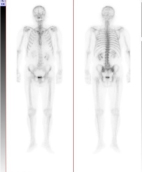

■骨シンチグラフィ

骨シンチグラフィとは、骨に集まる放射性薬剤を静脈投与した後、放射性薬剤の集積程度を特殊なカメラ(ガンマカメラ)で撮像することにより、骨の状況(癌による骨転移、骨折、骨髄炎など)を調べる検査です。レントゲンよりも早期に骨の異常を見つけることができます。

正常例

多発性骨転移症例